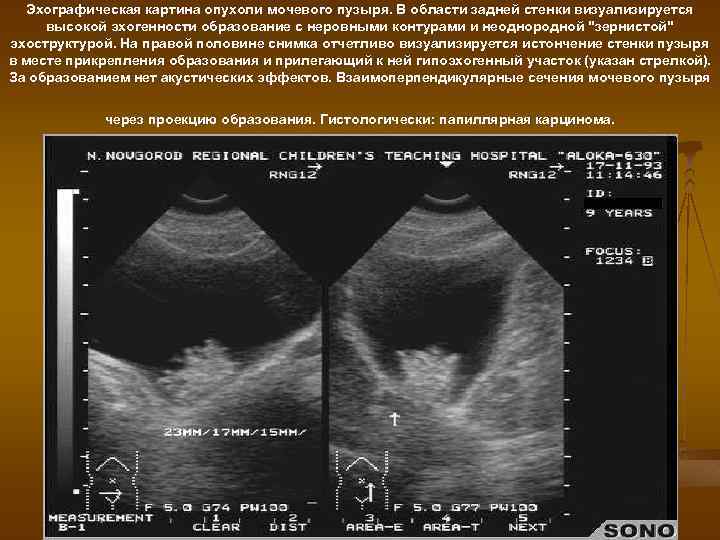

Эхографическая картина опухоли мочевого пузыря. В области задней стенки визуализируется высокой эхогенности образование с неровными контурами и неоднородной "зернистой" эхоструктурой. На правой половине снимка отчетливо визуализируется истончение стенки пузыря в месте прикрепления образования и прилегающий к ней гипоэхогенный участок (указан стрелкой). За образованием нет акустических эффектов. Взаимоперпендикулярные сечения мочевого пузыря через проекцию образования. Гистологически: папиллярная карцинома.